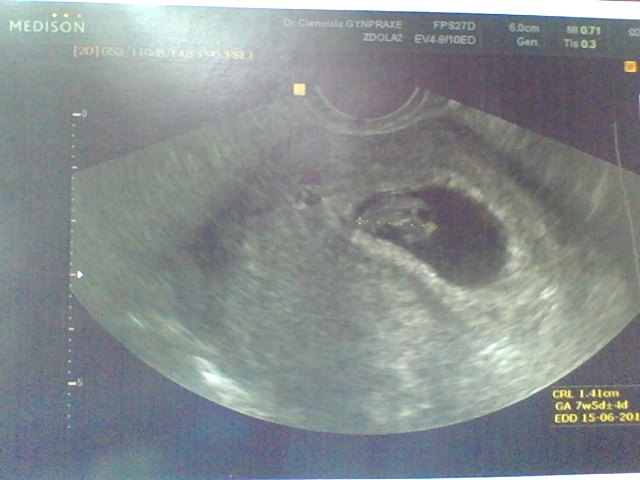

Ahojky maminky tak mě dnes spadlo půl kamene ze srdce. byla jsem u dr a srdíčko jsme viděli a vše je v pořádku. přikládám fotečku. ještě to doklepat do toho screeningu a spadne mi celý balvan. díky moc za podporu. :D